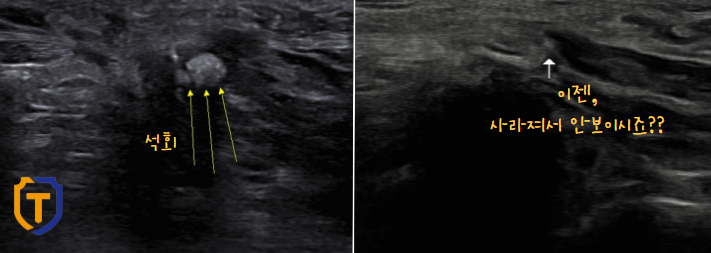

체외 충격파 후, 손목 경과

전, 후가 확연한 차이가 보이네요!

초음파상 덩어리는 없어지고, 가루들만 조금 남아보입니다.